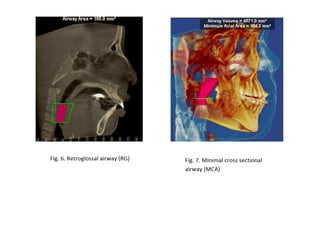

RME

• Maxillary constriction in particular has been

postulated to play a role in the pathophysiology

of OSA because of its association with low tongue

posture that may contribute to the orophayrnx

airway narrowing (Subtelny 1954).

• Pirelli et al. grouped 31 children with OSA and

followed them up to 4 months after RME

treatment. All of these children had their apnea-

hypoapnea index decreased while their mean

maxillary cross sectional width expanded to

about 4.5mm.